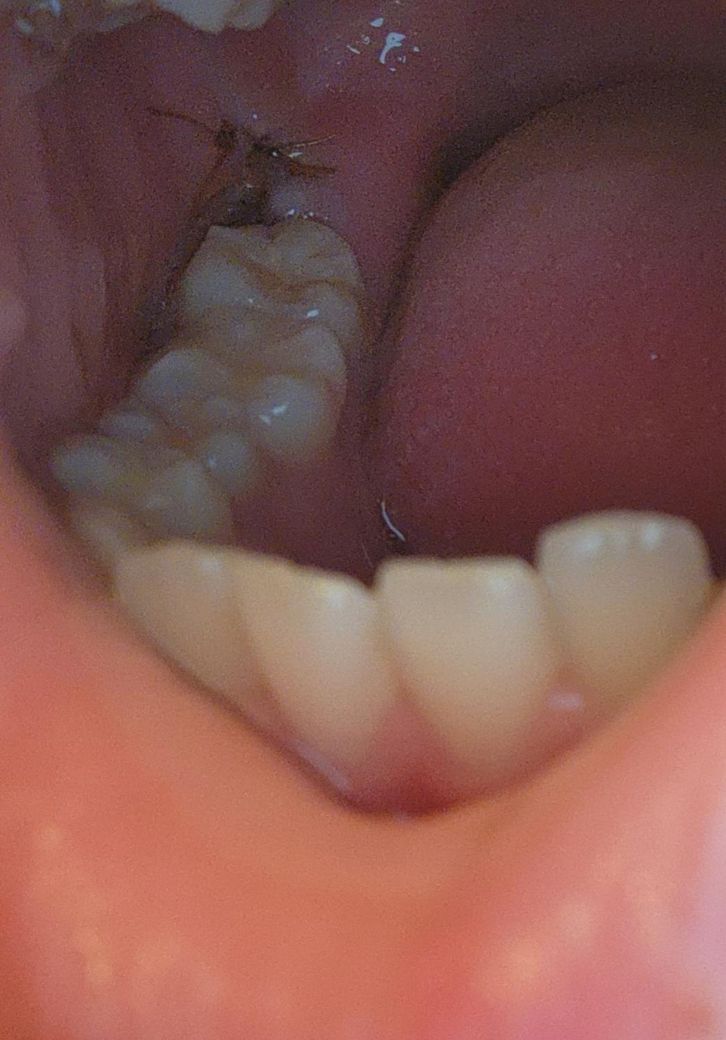

어제 발치했고 오늘로 이틀차인데 봉합면에 하얗게? 뭐가 생겼어요. 양치하고 나서도 잠시 따가운데 정상인가요? 사진 화질도 안좋고 좀 어두워요..

잇몸이 아무는 과정에서 잇몸에 하얗게 가피등이 형성될수 있습니다 사진으로는 정확한 확인이 어려워 보이나 크게 문제가 있는것으로 보이지는 않습니다. 발치를 했다면 발치한 부위가 자극되지 않도록 하는것이 좋습니다

잇몸 부위에 염증이 생긴 것으로 보입니다. 발치 후 발치 부위에 생길 수 있는 흔한 잇몸 염증입니다. 물 가글 살살해서 위생관리 잘해주시기 바랍니다.

어제 발치하셨다면 불편하고 아플 수 있습니다. 사진상으로 보기에는 문제없이 잘 아물고 있으니 걱정하지 않으셔도 되겠습니다.